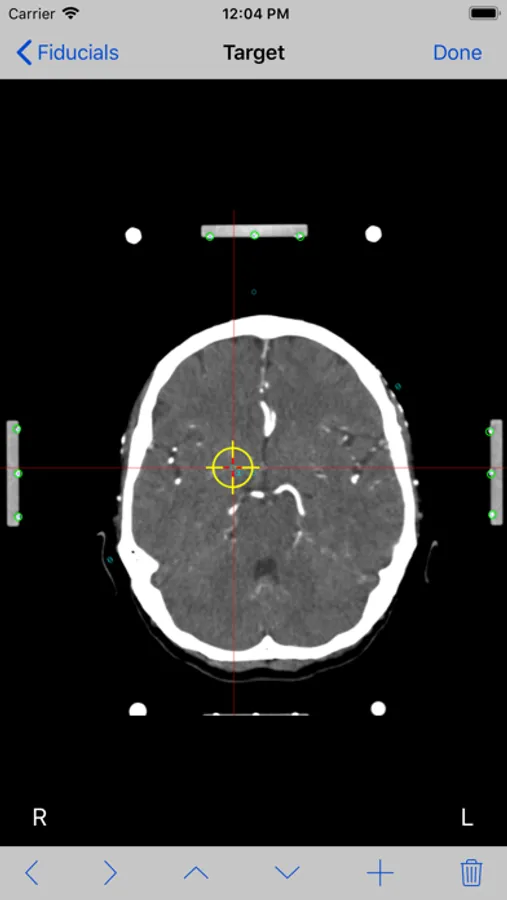

8. Mark the target point you want to reach and tap the Done button.